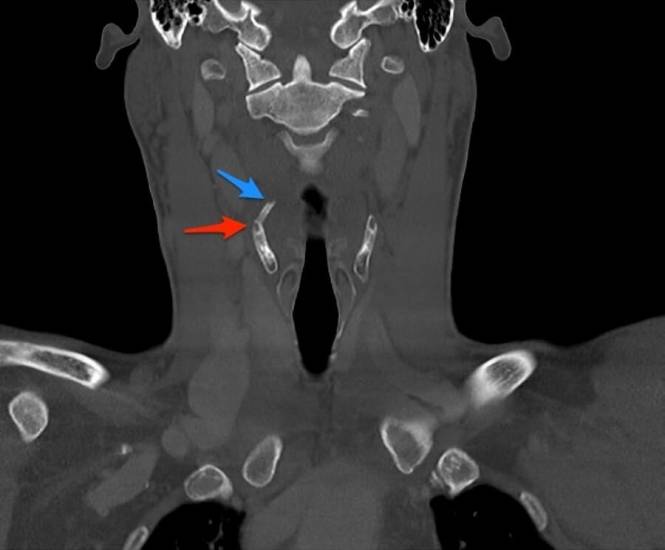

Диагноз ставит врач отоларинголог на основании клинического обследования и дополнительных данных. При небольшом размере ларингоцеле признаки вообще могут отсутствовать. Его случайно обнаруживают при ларингоскопии по поводу другого обращения к врачу или на снимках КТ, рентгена.

Ларингоцеле КТ-снимок

Для подтверждения диагноза ларингоцеле гортани используют КТ, МРТ и рентгенографию. Эти методы помогают дифференцировать ларингоцеле от других образований в гортани и соседних органах, таких как опухоли и абсцессы. На снимках можно оценить размеры кисты и ее расположение относительно окружающих тканей. На КТ ларингоцеле выглядит как полость с гладкими стенками, содержащая воздух.